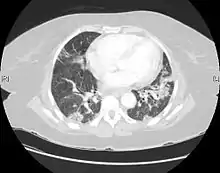

CT scan of a patient with UIP. There is interstitial thickening, architectural distortion, honeycombing and bronchiectasis. | |

UIP may be diagnosed by a radiologist using computed tomography (CT) scan of the chest, or by a pathologist using tissue obtained by a lung biopsy.

Radiologically, the main feature required for a confident diagnosis of UIP is honeycomb change in the periphery and the lower portions (bases) of the lungs.[3]

On high-resolution computed tomography (HRCT), the following categories, depending on imaging findings, have been recommended by a collaborative effort by the American Thoracic Society, European Respiratory Society, Japanese Respiratory Society, and the Latin American Thoracic Society:[4]

- UIP pattern:[4]

- Honeycombing, with or without peripheral traction bronchiectasis; or bronchiolectasis (dilatation of the terminal bronchioles)[5]

- Predominantly subpleural and basal

- Often heterogenous distribution, being occasionally diffuse, and may be asymmetrical

There may be superimposed CT features such as mild ground-glass opacity, reticular pattern and pulmonary ossification.